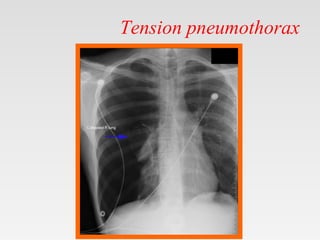

Tension pneumothorax

• Tension pneumothorax is classically characterized by

hypotension and hypoxia.

• It is life threatening condition.

• Rapidly progressive breathlessness and circulatory

collapse (tachycardia, hypotension & sweating).

• Jugular venous distention

• The pleural pressure is more than the atmospheric pressure.

Radiological manifestations of large pneumothorax

• Mediastinal shift,

• Flattening of the hemidiaphragm &

• Lung collapse.

It is more common with

• Positive pressure ventilation &

• Traumatic pneumothorax.